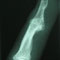

Gelenkveränderungen und rheumatische Zerstörungen am Fuß bedürfen besonderer Sorgfalt. Am Sprunggelenk sind neben Entfernung der Gelenkinnenhaut (arthroskopisch), Knorpeloperationen und Spornabfräsungen unter Umständen auch Gelenkversteifungsoperationen durchzuführen. Durch die moderne Fußchirurgie sind wir häufig in der Lage, selbst schwerste Zerstörungen wieder ins rechte Lot zu rücken und gangbar zu machen. Manchmal ist aber auch "nur" eine Krallenzehe oder ein Überbein zu korrigieren. Jeder Fuß ist individuell und bedarf der genauen Planung. Nicht jeder Fußschmerz muss operiert werden, manchmal hilft auch die richtige Einlage und der richtige Schuh - wir werden Sie beraten.